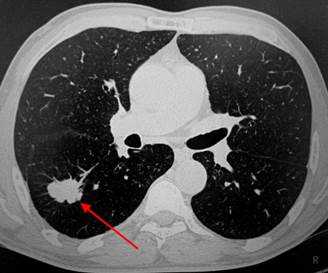

КТ-признаки туберкуломы легкого. Образование диаметром 2 см расположено в правом легком. Отличить туберкулому от рака помогает наличие глыбчатых кальцинатов (извести) в структуре образования, четкие контуры, окружающие фиброзные тяжи, а также мелкие очаги отсева вокруг.

Рентгенография при раке легкого выявляет округлую тень слева. С целью дифференциальной диагностики (отличить рак легкого от туберкуломы, кисты или пневмонии) необходимо выполнять компьютерную томографию — КТ.